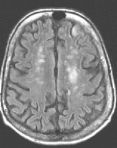

MRI Findings: In the supratentorial regions, some atrophy and chronic small vessel deep white matter ischemic changes were observed (Fig. 1) but no acute lesion or infarct was observed on MR diffusion. In the posterior fossa, however, a subtle small 1 cm hyperintensity can be seen in the left side of medulla on T2 weighted (Fig. 2) and FLAIR images (Fig. 3). This can be seen with an infarct, but its age would remain indeterminate. The MR diffusion image (Fig. 4) shows hyperintensity in the same region consistent with an acute infarct (arrows) as opposed to chronic ischemic changes.